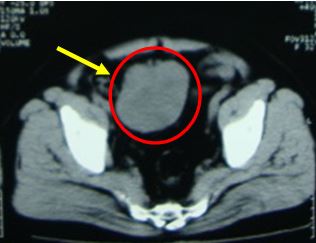

+ Bệnh nhân được tiến hành chụp cắt lớp vi tính ổ bụng để đánh giá cho thấy hình ảnh khối giảm tỷ trọng kích thước 70x90x100 mm, ranh giới rõ, bờ thùy múi, ngấm thuốc cản quang sau tiêm, trung tâm có vùng hoại tử không ngấm thuốc, khối u đè đẩy bàng quang ra sau và sang trái

Kết luận: Khối u vùng tiểu khung theo dõi lymphoma

Hình 2. Hình ảnh chụp cắt lớp vi tính ổ bụng: Khối u vùng hạ vị đè một phần vào bàng quang, đẩy bàng quang ra sau và sang trái